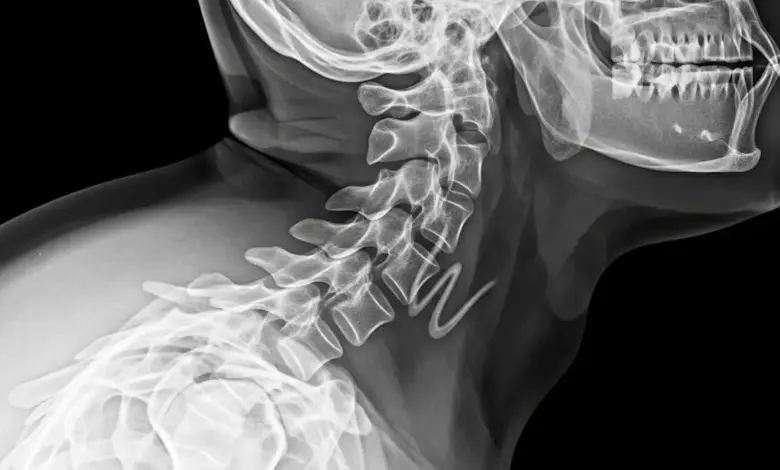

A síndrome de Klippel-Feil é uma condição congênita caracterizada pela fusão de duas ou mais vértebras cervicais, o que pode gerar pescoço curto, linha de implantação capilar baixa e limitação de movimento.

Em vez de vértebras separadas por disco e cartilagem, ocorre fusão óssea em níveis do pescoço, às vezes com extensão para a coluna torácica ou lombar.

- Radiografias em AP, perfil e odontoide, para mapear níveis fundidos e curvaturas.

- Tomografia, quando é preciso detalhar anatomia óssea pré-operatória.

- Ressonância magnética, para avaliar medula, raízes nervosas, estenose e malformações.